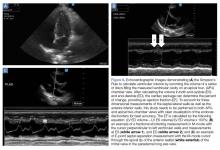

Figure 6.

Fractional Shortening

M-mode ultrasound can be used in several ways to estimate LV EF. Fractional shortening (FS) estimates the size reduction of the LV during systole. In the parasternal long axis (PLAX) view, the M-mode cursor is placed over the walls of the LV, just apical to the tips of the mitral valve (MV) leaflets ( Figure 6b ). Maximal (end-diastolic diameter [EDD]) and minimal (end-systolic diameter [ESD]) dimensions of the LV are measured and FS is calculated as (LVEDD – LVESD)/ LVEDD. A normal value is more than 25%, and a rough estimate of EF is FS x 2. 24 Limitations to this study include nonplacement of the M-mode cursor perpendicular to the LV walls, and inaccuracy in patients with regional wall abnormalities.

E-Point Septal Separation

Another way to assess EF with POCUS is through E-point septal separation (EPSS), which uses the movement of the MV during diastole to estimate the EF during systole. In the PLAX view, the M-mode cursor is placed over the apical tip of the anterior leaflet of the MV to visualize the movement of the leaflet in relation to the interventricular septum ( Figure 6c ). Two characteristic waves are created during each diastole—the larger first wave representing early filling (the E-wave) and the smaller second wave representing the atrial kick (the A-wave). The E-point is the tallest point of the E-wave, and the EPSS is measured as the distance in millimeters between the E-point and the interventricular septum. 21

The opening of the anterior leaflet of the MV toward the interventricular septum in diastole requires a pressure difference between the left atrium (LA) and LV. In a patient with poor LV systolic function, the LV is still full at the end of systole, the pressure difference is not as great, and the mitral leaflets will not snap open vigorously. The EPSS should be at or less than 6 mm in patients with normal LV systolic function. An EPSS of 6 to 12 mm suggests moderately depressed LV systolic function, and over 12 mm signifies severely decreased LV systolic function. 25 Limitations include inaccuracy in patients with valvular abnormalities, such as mitral stenosis or aortic regurgitation, severe LV or septal hypertrophy, regional wall abnormalities or severe LV dilation, limited data, and a wide margin of error when comparing to magnetic resonance imaging measurement of EF.